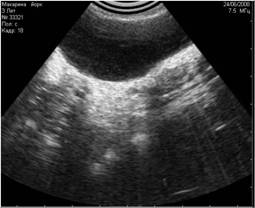

Рис. 8. На снимке представлен гиперэхогенный объект в полости мочевого пузыря, испускающий эхоакустическую тень. На основании этого артефакта, мы можем предположить, что этот объект является конкрементом. |

Рис. 9. На снимке представлен похожий по величине и эхогенности объект в полости мочевого пузыря, не испускающий эхоакустической тени. На основании этого признака, мы можем предположить, что изучаемый объект является новообразованием. |